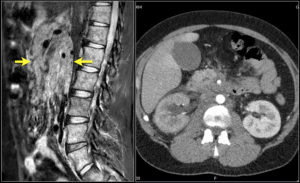

Диагноз устанавливают при наличии характерных клинических признаков признаков. Диагноз подтверждают с помощью лапароскопии. Большое диагностическое значение имеют ультразвуковое исследование органов брюшной полости и компьютерная томография. Однако чаще правильный диагноз устанавливают только в результате интраоперационной биопсии мезентериальных лимфатических узлов.

Компьютерное обследование показывает, в каком состоянии находится брюшина. УЗИ поможет разобраться с определением больного органа. Если есть подозрение на наличие туберкулёзных бацилл, делают пробу Манту. Диагностическая лапароскопия назначается для визуализации поражённых связок, осмотра соседних органов, с целью выявления сопутствующей патологии.

Проверенным методом диагностики считается МРТ. Этот способ считается точным, информативным решением проблемы по выявлению патологии. С его помощью можно подсчитать количество поражённых лимфатических сосудов, измерить размеры их деформации. Визуально обследовать изменения в работе желудочно-кишечного тракта и соседних органов.